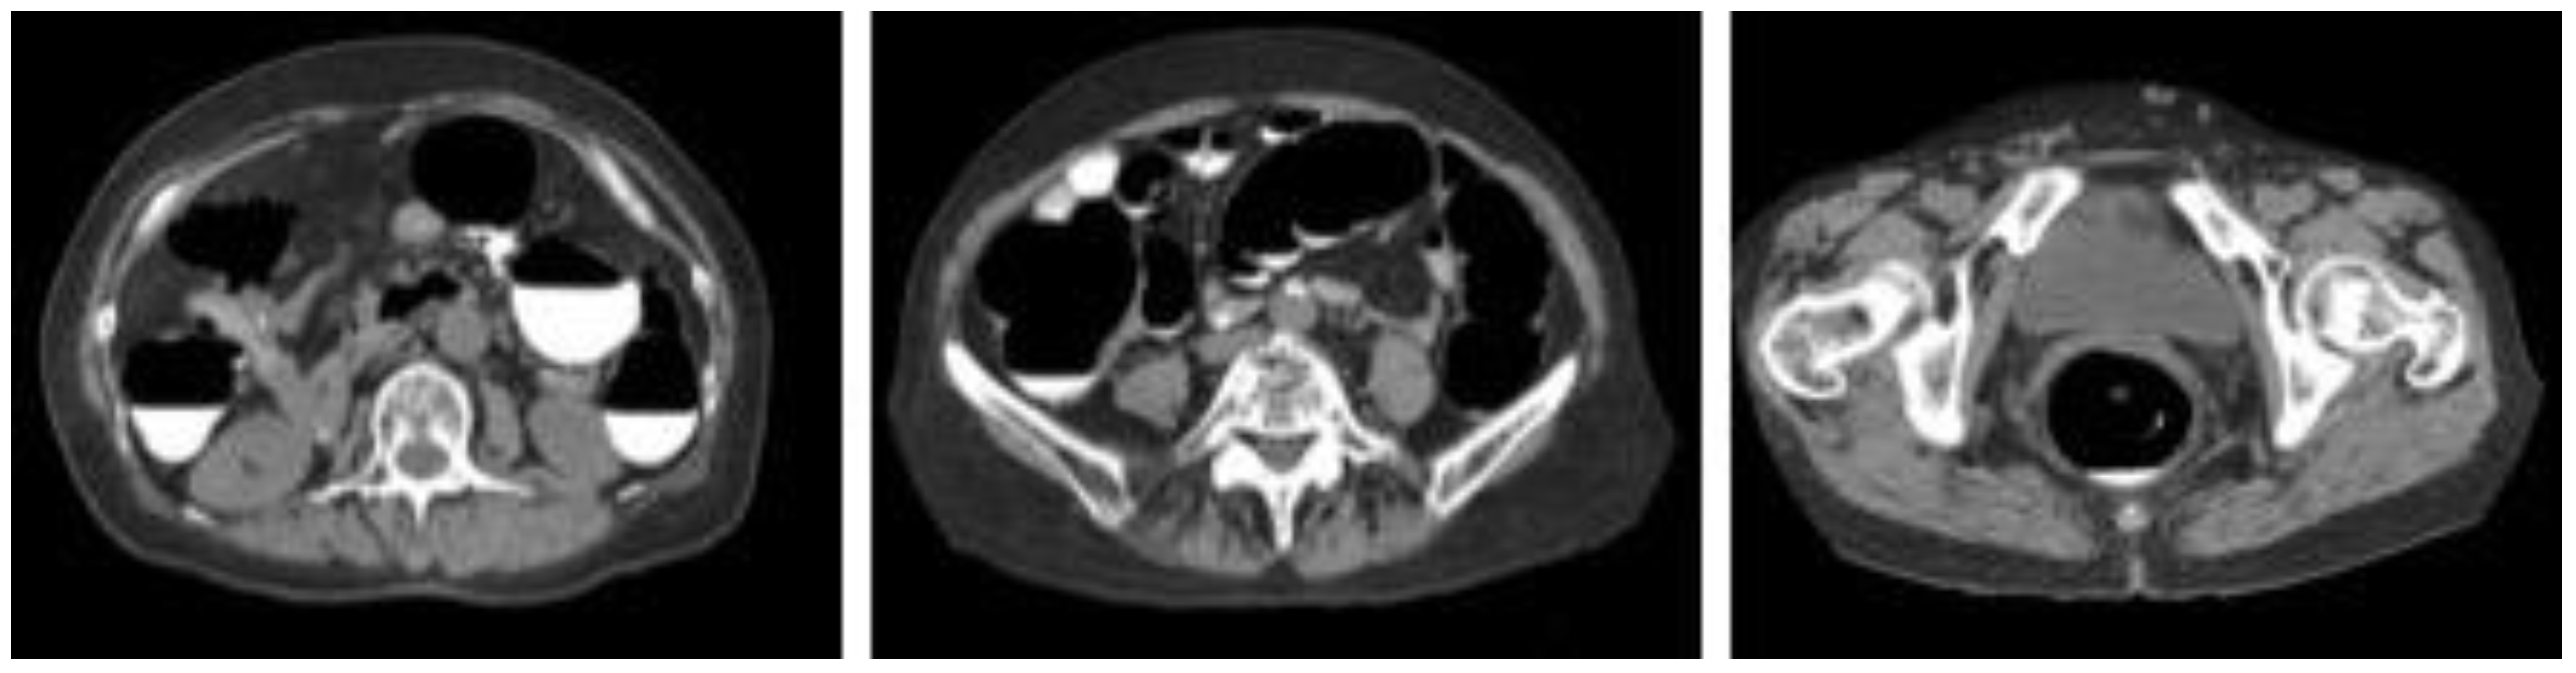

We collected images of 125 cases of CTC taken at the Yokkaichi Hazu Medical Center of the Japan Community Health Care Organization. Figure 1 shows the original CTC images collected in this study. One hundred cases were used for CycleGAN training, and the remaining 25 cases were used for evaluation. The data acquisition period for the 100 cases was from 20 April 2021 to 13 September 2021, and the data acquisition period for the 25 cases for validation was from 20 November 2021 to 15 January 2022.

Figure 1.

Sample images of collected computed tomography dataset.